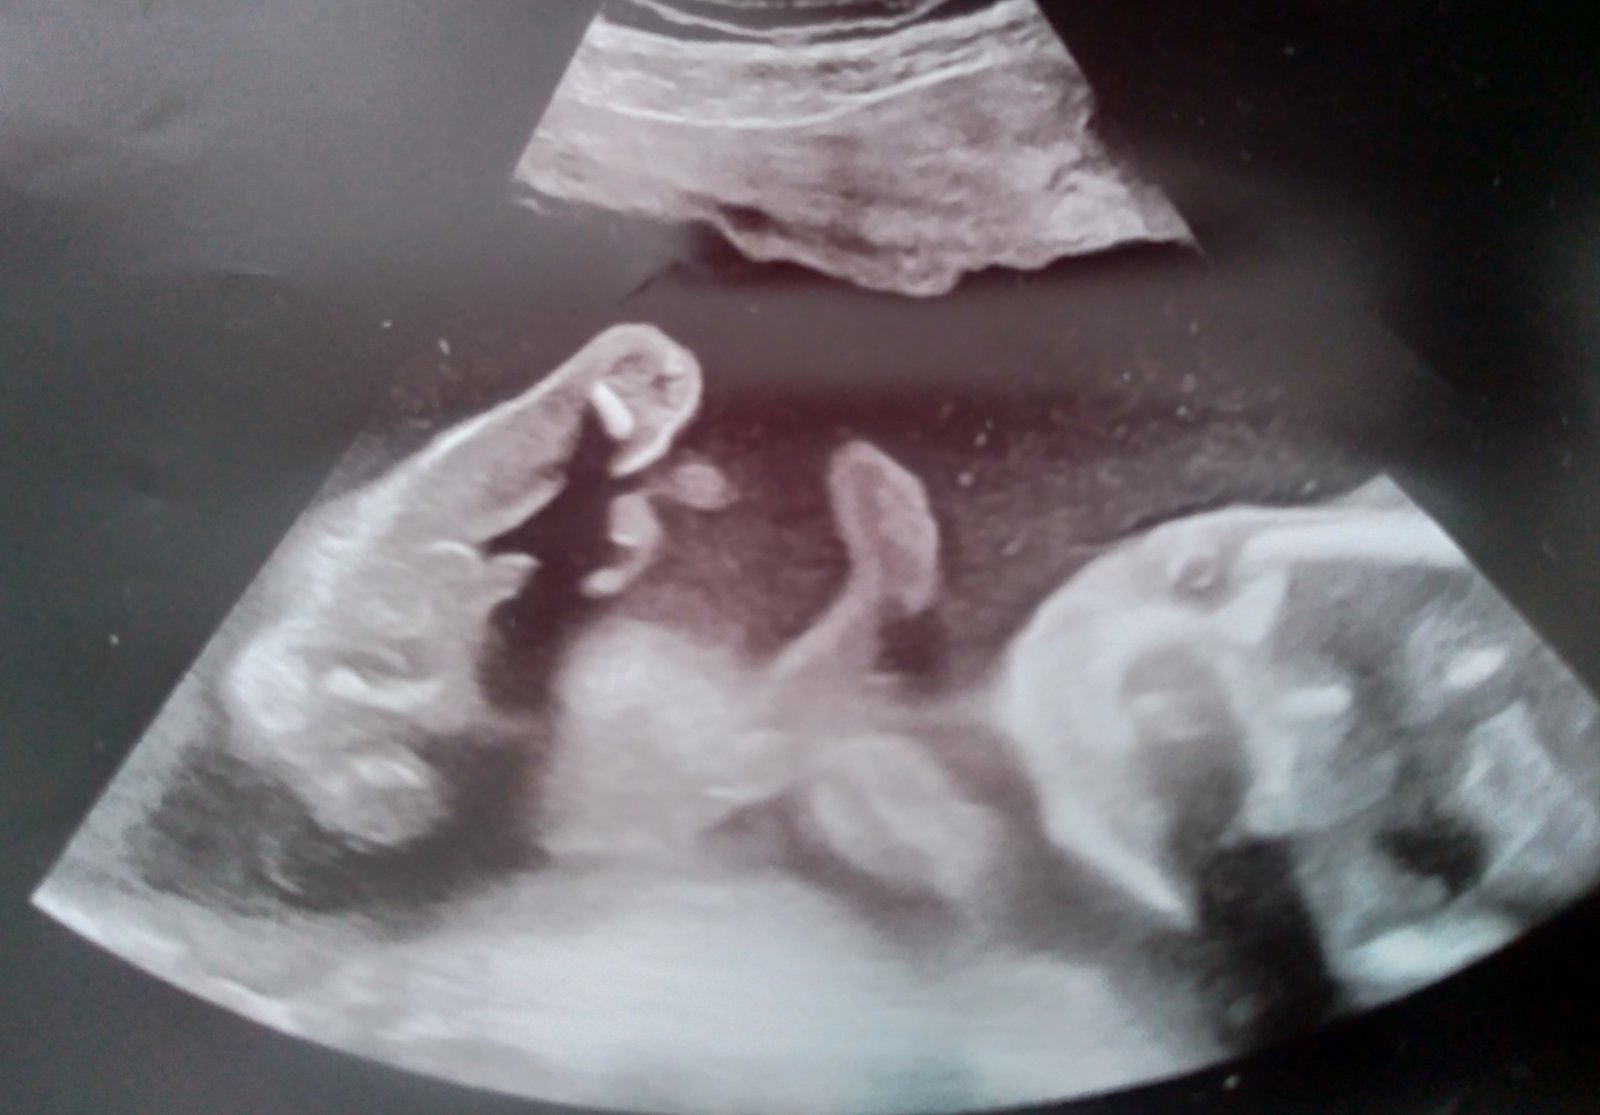

Ahoj holky,

tak dneska jsme byli na ultrazvuku v 20.tt. Bylo tam vidět tohle ...No paní doktorka nám řekla, že by zatím nedělala závěry, co to bude a že máme počkat.

Jasně, že počkáme na doktora, ale jsem strašně zvědavá. A hlavně...asi tam vidím pindíka 😁 Tak na to prosím taky koukněte, jestli jsem si to nevsugerovala 😁